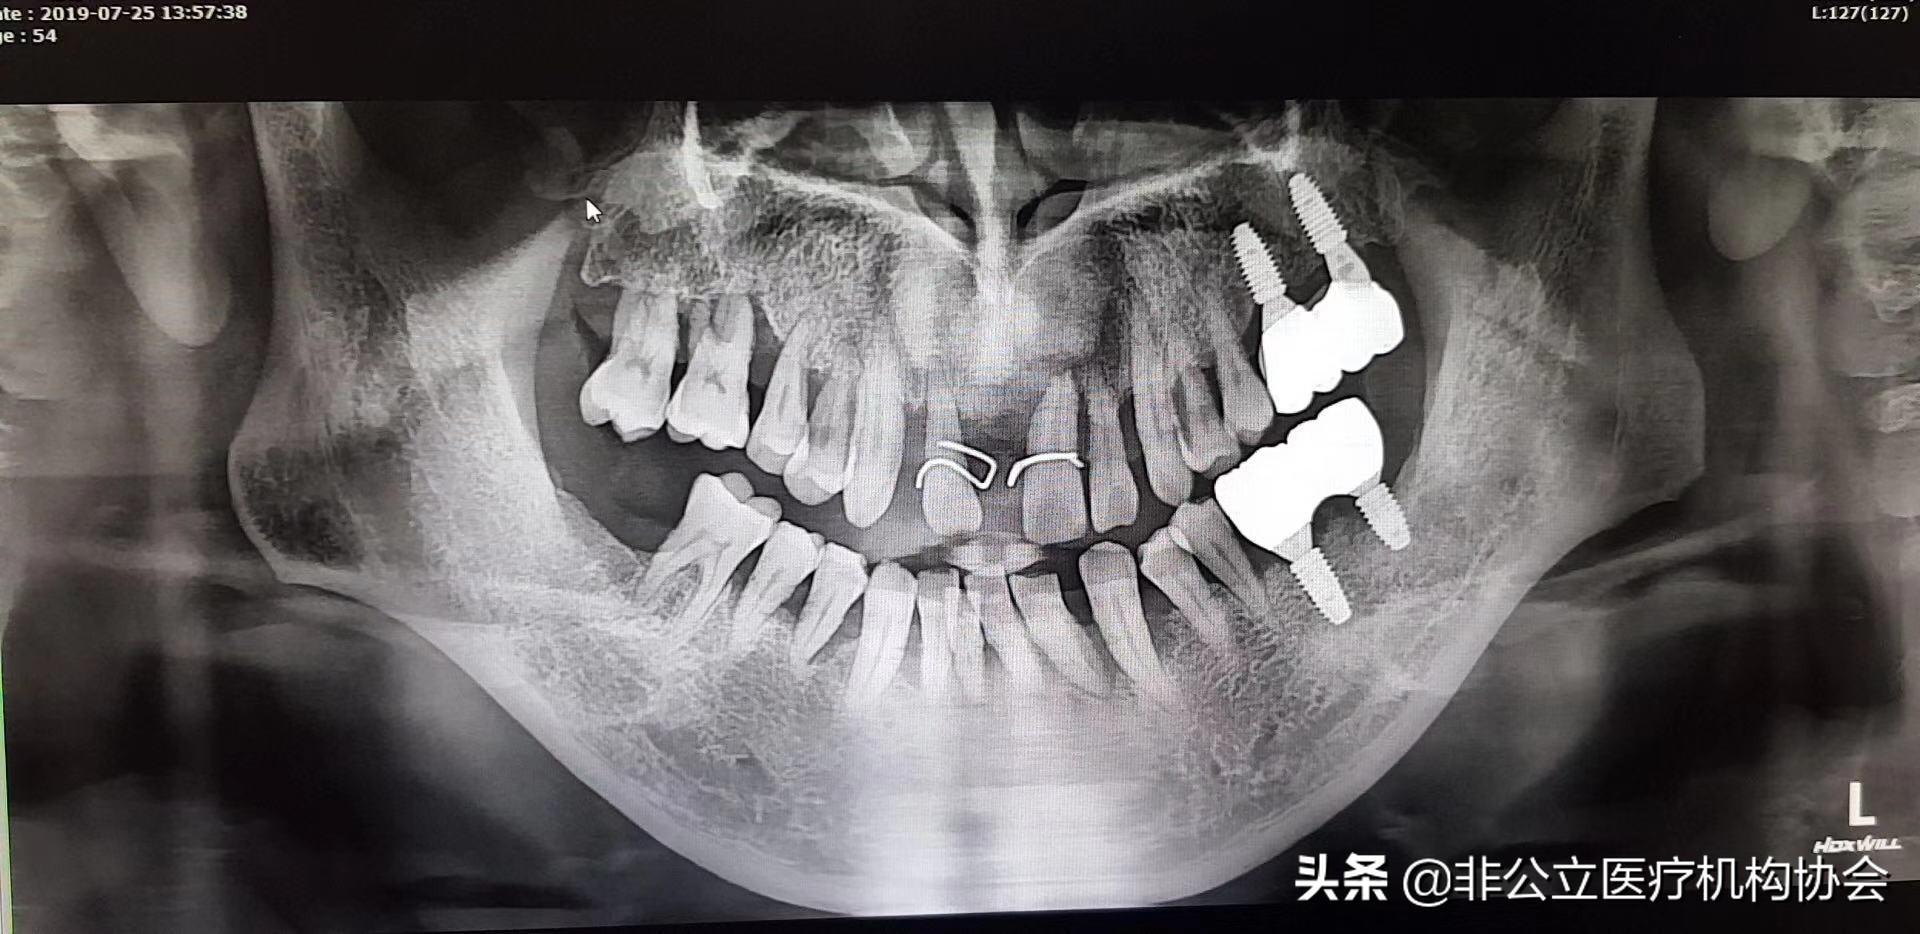

【此病例分為兩部分,這是第一部分】術(shù)前的X光片,54歲男,種四顆了,上下前牙。上下前牙牙周病了((一)

檢查:上下1、23度松動(dòng),排列不齊,牙石2度?,牙齦紅腫,輕探出血,CT 檢查水平吸收達(dá)根長(zhǎng)1/3左右。有牙槽骨吸收。嚴(yán)重牙周病。